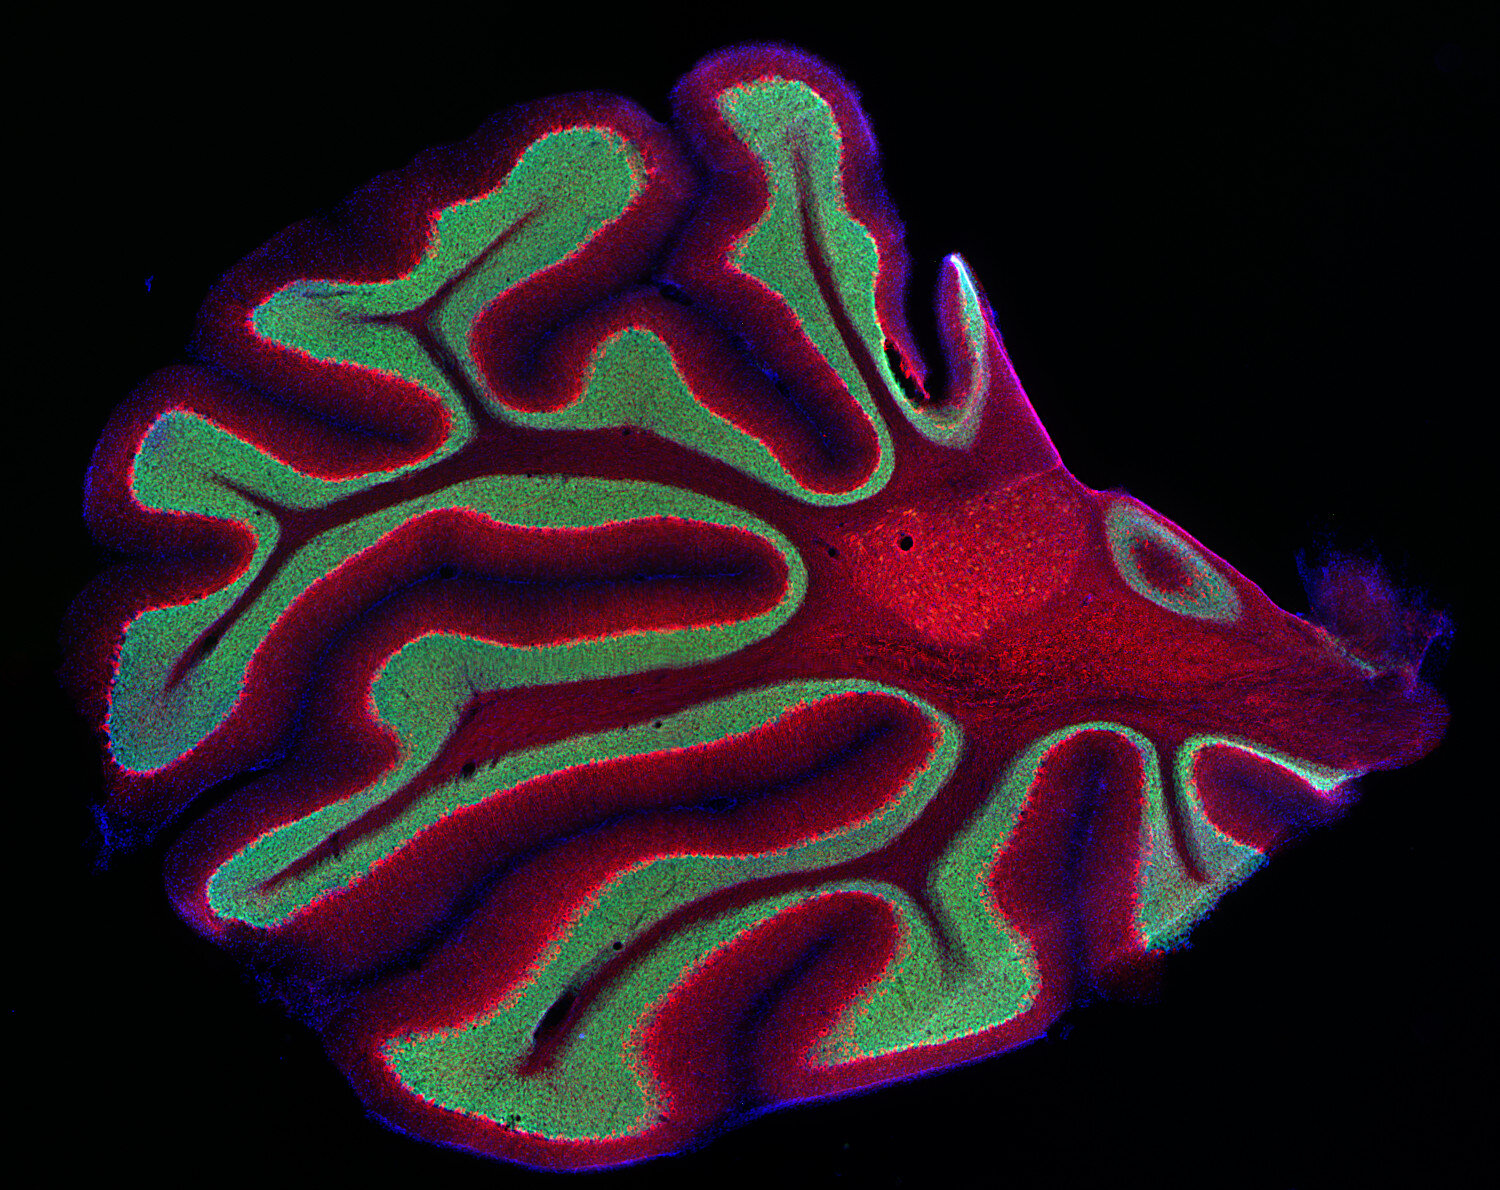

IHC: 1 : 500 gallery

Immunohistochemistry (IHC) on 4% PFA perfusion fixed tissue with 24h PFA post fixation. Immunoreactivity is usually revealed by fluorescence or a chromogenic substrate. Some antibodies require special fixation methods or antigen retrieval steps. For details, please refer to the ”Remarks” section.

Neurofilaments (NFs) are intermediate filaments essential for providing structural support to neurons, particularly within axons. They play a crucial role in maintaining axonal diameter, which directly influences nerve conduction velocity (1). Neurofilaments are composed of three primary subunits - NF-L (light), NF-M (medium) and NF-H (heavy) – along with an NF-associated protein. In the adult central nervous system (CNS), α-internexin serves as the fourth neurofilament subunit, whereas in the peripheral nervous system (PNS), peripherin takes on this role (2).

Beyond their structural function, neurofilaments are also valuable biomarkers in both research and clinical settings. They are widely used in immunohistochemistry to stain and visualize axons, particularly in peripheral nerves and the CNS. Increased levels of neurofilament proteins in cerebrospinal fluid (CSF) or blood are strongly associated with neurodegenerative diseases, such as amyotrophic lateral sclerosis (ALS), multiple sclerosis (MS), and Alzheimer’s disease (3). In peripheral nerve studies, neurofilament staining is often combined with other markers, such as S100, to provide a more comprehensive assessment of nerve structure and pathology (4).